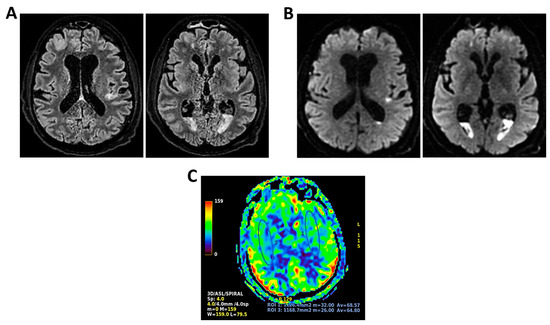

Background: Meningoencephalitis is a complex inflammatory condition of the CNS that can result in significant morbidity and mortality in critically ill adults. Accurate and timely neuromonitoring is essential for guiding management and improving outcomes. This study aimed to descriptively evaluate the prognostic value of early TCCD monitoring, particularly the pulsatility index, and its integration with conventional and perfusion MRI in patients with meningoencephalitis. Methods: We present an observational, retrospective, cohort study involving ten adult patients (median age 56 years, IQR 45.5–68.5; mean 55.9, range 35–76) with neurological syndromes caused by suspected or confirmed infectious meningoencephalitis. Etiologies included bacterial meningitis/meningoencephalitis (50%), viral meningoencephalitis (10%), neurotoxoplasmosis (10%), progressive multifocal leukoencephalopathy (10%), and undetermined origin (20%). Patients underwent TCCD and MRI within 24 h. In five cases, standard MRI sequences were acquired, while in the remaining five, perfusion imaging was performed using Arterial Spin Labelling (ASL). A favorable outcome was defined as survival with neurological recovery (Glasgow Outcome Scale > 5) at ICU discharge. Results: TCCD-derived PI provided valuable information on cerebral hemodynamics. PI values ≤ 1.25 were associated with favorable clinical outcomes and symmetrical MRI findings. Conversely, PI > 1.25 correlated with poor prognosis and often preceded MRI-detectable structural damage. When combined with ASL, PI mirrored the detected perfusion asymmetries and was associated with poor prognosis in fatal cases. Conclusions: Bedside TCCD can offer real-time assessment of cerebrovascular dynamics and, when integrated with conventional and ASL MRI, could enhance the understanding of pathophysiological processes in meningoencephalitis, supporting timely and informed decisions in neurocritical care.